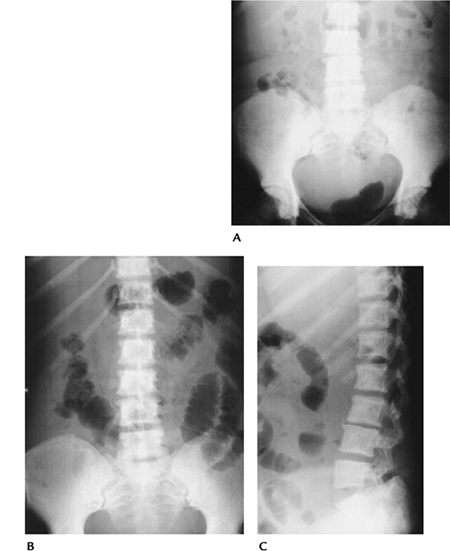

FIGURE 15-10 Mastocytosis. (A)

AP radiograph of the lumbar spine and pelvis showing generalized bone sclerosis and cortical thickening. There are more focal foci of sclerosis in the femoral heads. AP (B) and lateral (C) radiographs of the lumbar spine and pelvis in a different patient showing diffuse small sclerotic foci. |